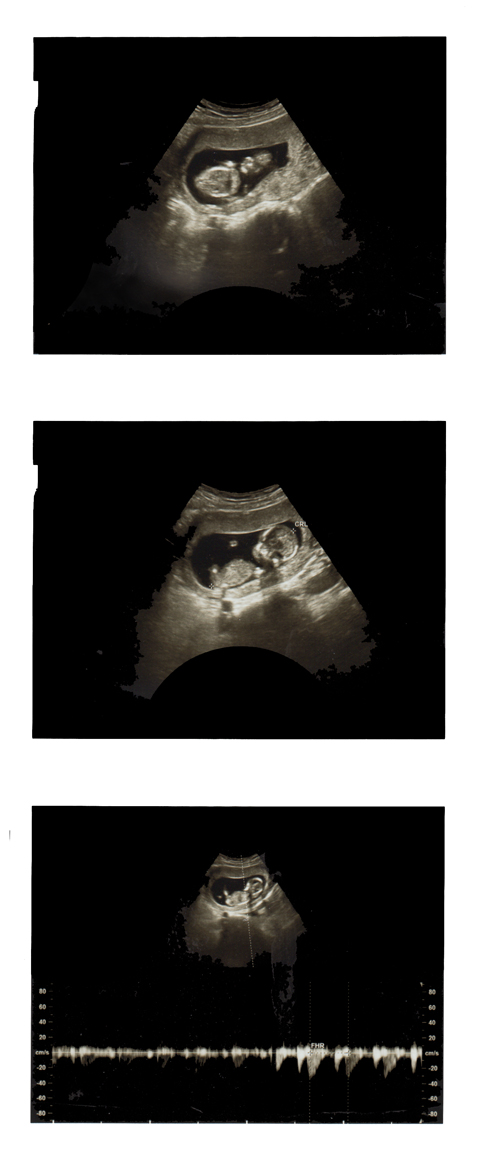

Here's a 3D image our doctor took! Pretty crazy, huh?!?!

Anyway, we are 15 weeks along! Crazy, crazy, cRaZy! We're pretty stoked.